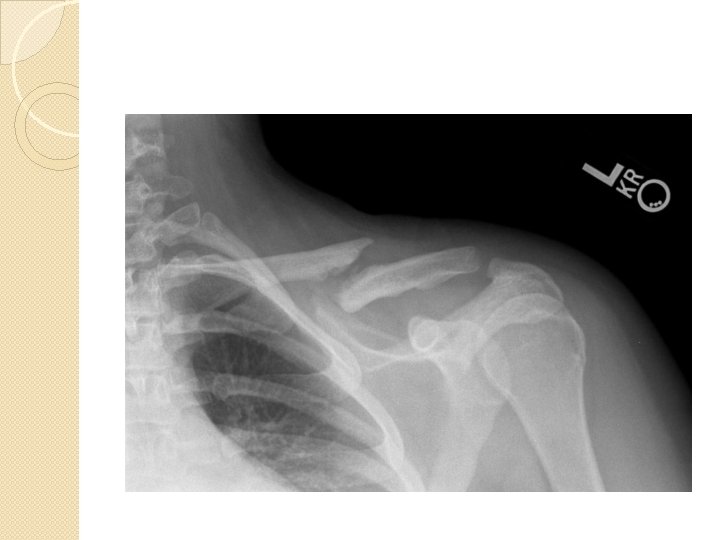

Ligament and Joint Injuries �AC Joint and GH Joint most commonly injured. �Acromioclavicular Joint Sprain ◦ “Separated shoulder” ◦ MOI: impact to top of shoulder; FOOSH; falling on bent elbow shoving head of Humerus up and into AC joint ◦ C/O P w/ ROM, “Step Deformity”

Step Deformity